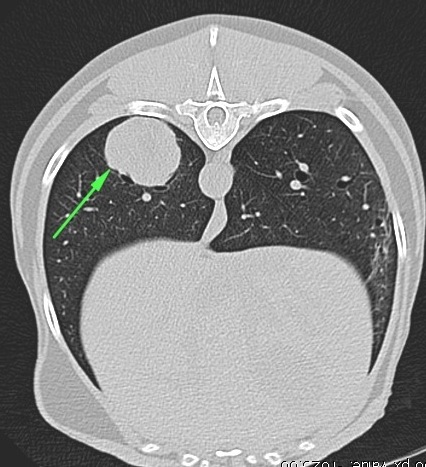

CT transverse view of chest

CT transverse view of the chest. The main right caudal

bronchus is partially occluded by a foreign body with

soft tissue density (green arrowheads). There is a mild

amount of gas bubbles trapped by the foreign body